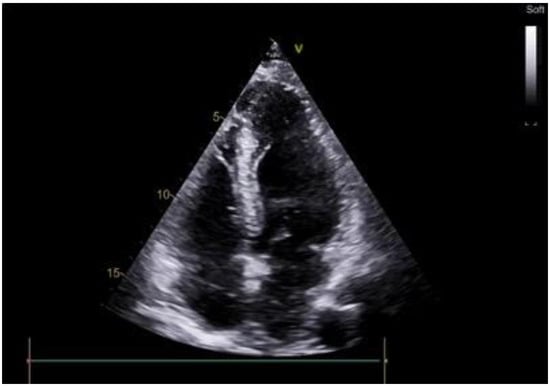

2.1. Case Scenario

2.2. Surgical Procedure

3. Results